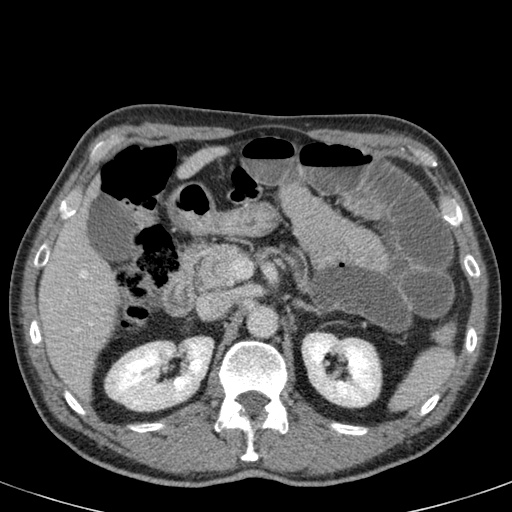

Bên trái là hình ảnh của một bệnh nhân bị xoắn đại tràng sigma.

Chúng ta có thể thấy đại tràng sigma giãn kéo dài từ vùng chậu lên tận góc phần tư trên bên phải.

Hãy quan sát hình ảnh và tự xác định tại sao đây không thể là xoắn manh tràng.

Sau đó tiếp tục.

Dấu hiệu then chốt là sự giãn của đại tràng đoạn gần.

Quai ruột giãn thấy ở bên trái chính là đại tràng ngang giãn.

Trên CT, chúng ta có thể thấy rõ vùng xoắn với đại tràng sigma kéo dài lên đến cơ hoành.

Đại tràng sigma là vị trí xoắn đại tràng thường gặp nhất.

Nó chiếm 75% các trường hợp tắc ruột già.